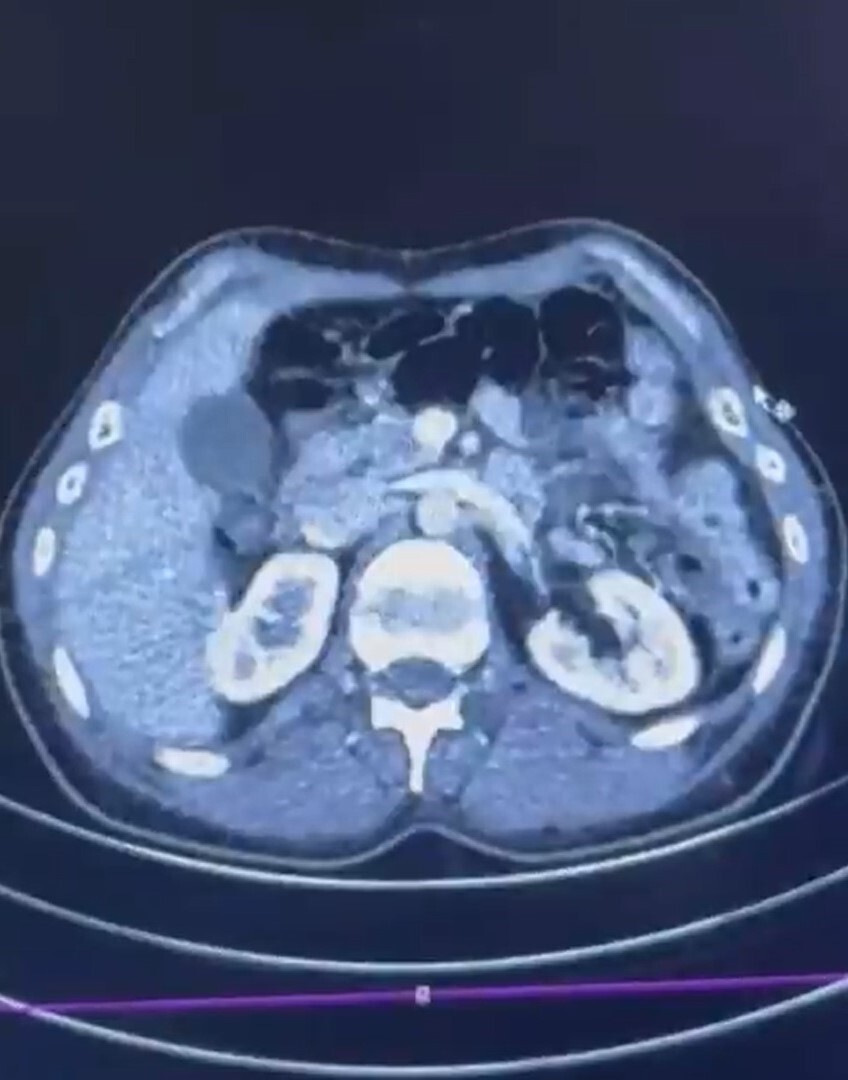

S.C. ve R.B.C.'nin Kayseri Şehir Hastanesi'nde yapılan iç beden muayenelerinde, mide bölgesinde 50 adet kapsül halinde toplam 554 gram uyuşturucu madde tespit edildi.

ŞÜPHELİLERİN MİDESİNDE KAPSÜL ŞEKLİNDE YARIM KİLO UYUŞTURUCU MADDE ELE GEÇİRİLDİ.